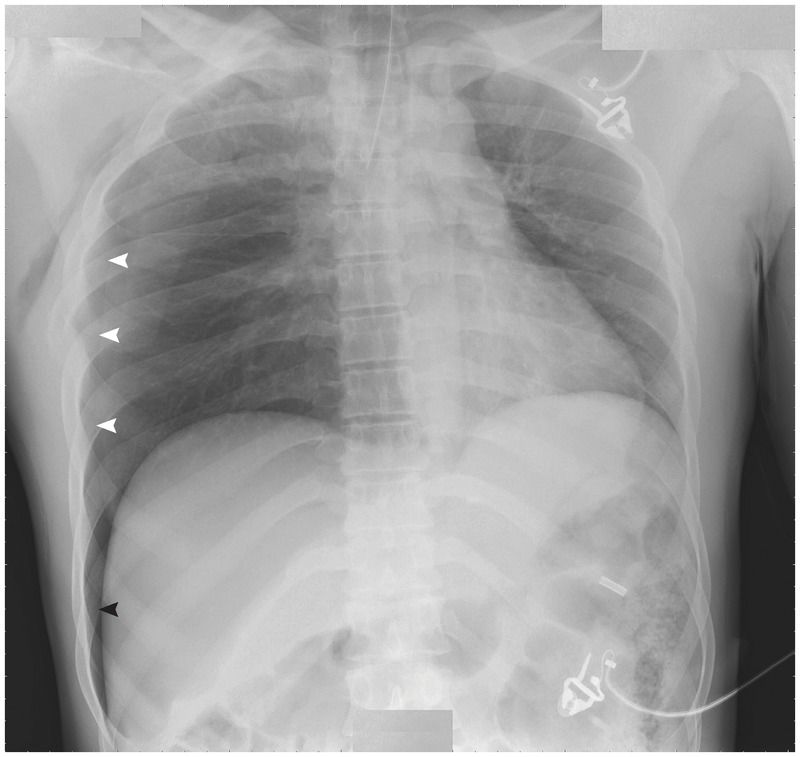

Chest radiography that was performed with the patient in the supine position showed a deep sulcus sign (black arrowhead), which was highly suggestive of a pneumothorax. On closer examination, a pneumothorax (white arrowheads) with associated rib fractures and subcutaneous emphysema were clearly evident.

The deep sulcus sign, which is characterized by a deep, lucent, ipsilateral costophrenic angle on supine chest radiography, is an indirect sign of a pneumothorax.

Intrapleural air distributes in a nondependent manner; thus, on upright radiographs, air collects in the apical lateral regions, and on supine radiographs intrapleural air collects initially in the anterior medial region and then in the lateral and caudal regions. The deep sulcus sign results from intrapleural air tracking in a laterocaudal manner.